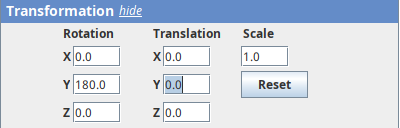

The transformation menu has controls for rotating, translating, and scaling the sample. We can either add values or manually interact with the 3D Animation window to reorient the sample. Let’s try the latter.

- Left-click on the head and move it around.

That’s a great way to see your sample from different angles. And note that the values in the Transformation panel get updated every time you move the sample interactively. In this way you can roughly position the sample and then check and update the precise values for the target transformation.

- Press

Resetand change theRotation Yto180to look at the right side of the head.